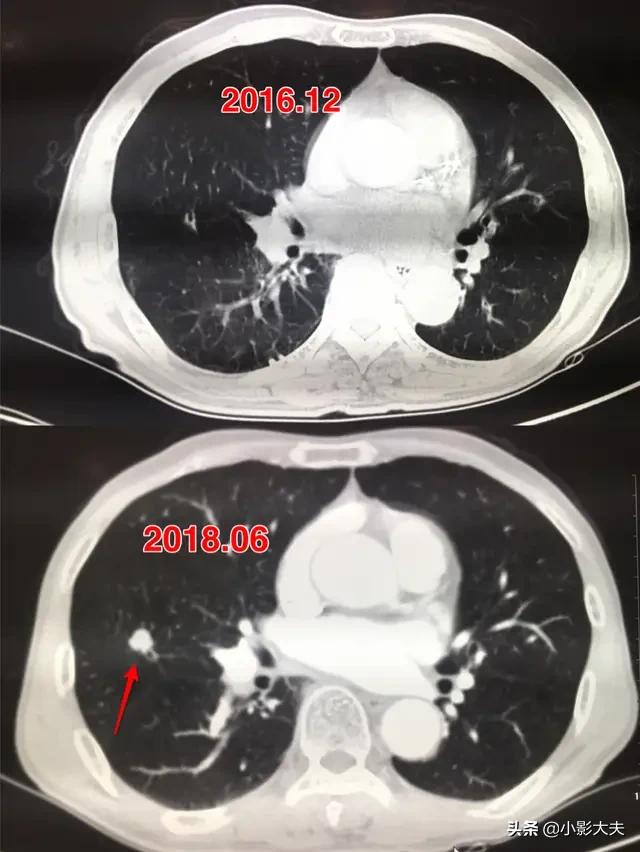

ここに肺結節の例を示しますが、肺結節が1cmに成長するまでの時間はすべて異なります。肺結節は良性結節と悪性結節に分けられます。悪性結節とは肺がんのことです。がんは良性結節よりも確実に早く成長します。肺がんには様々なタイプがあり、それほど悪性でなく成長が遅いものもあれば、非常に悪性で当然成長が早いものもあります。

上の結節と同様、発見から1年半で1cmまで成長した。